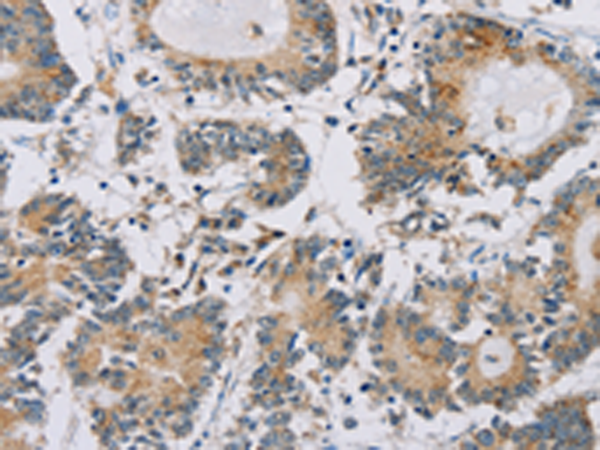

分类: 科研抗体货号: P08442别名: Imp4应用: WB,IHC反应种属: Human, Mouse